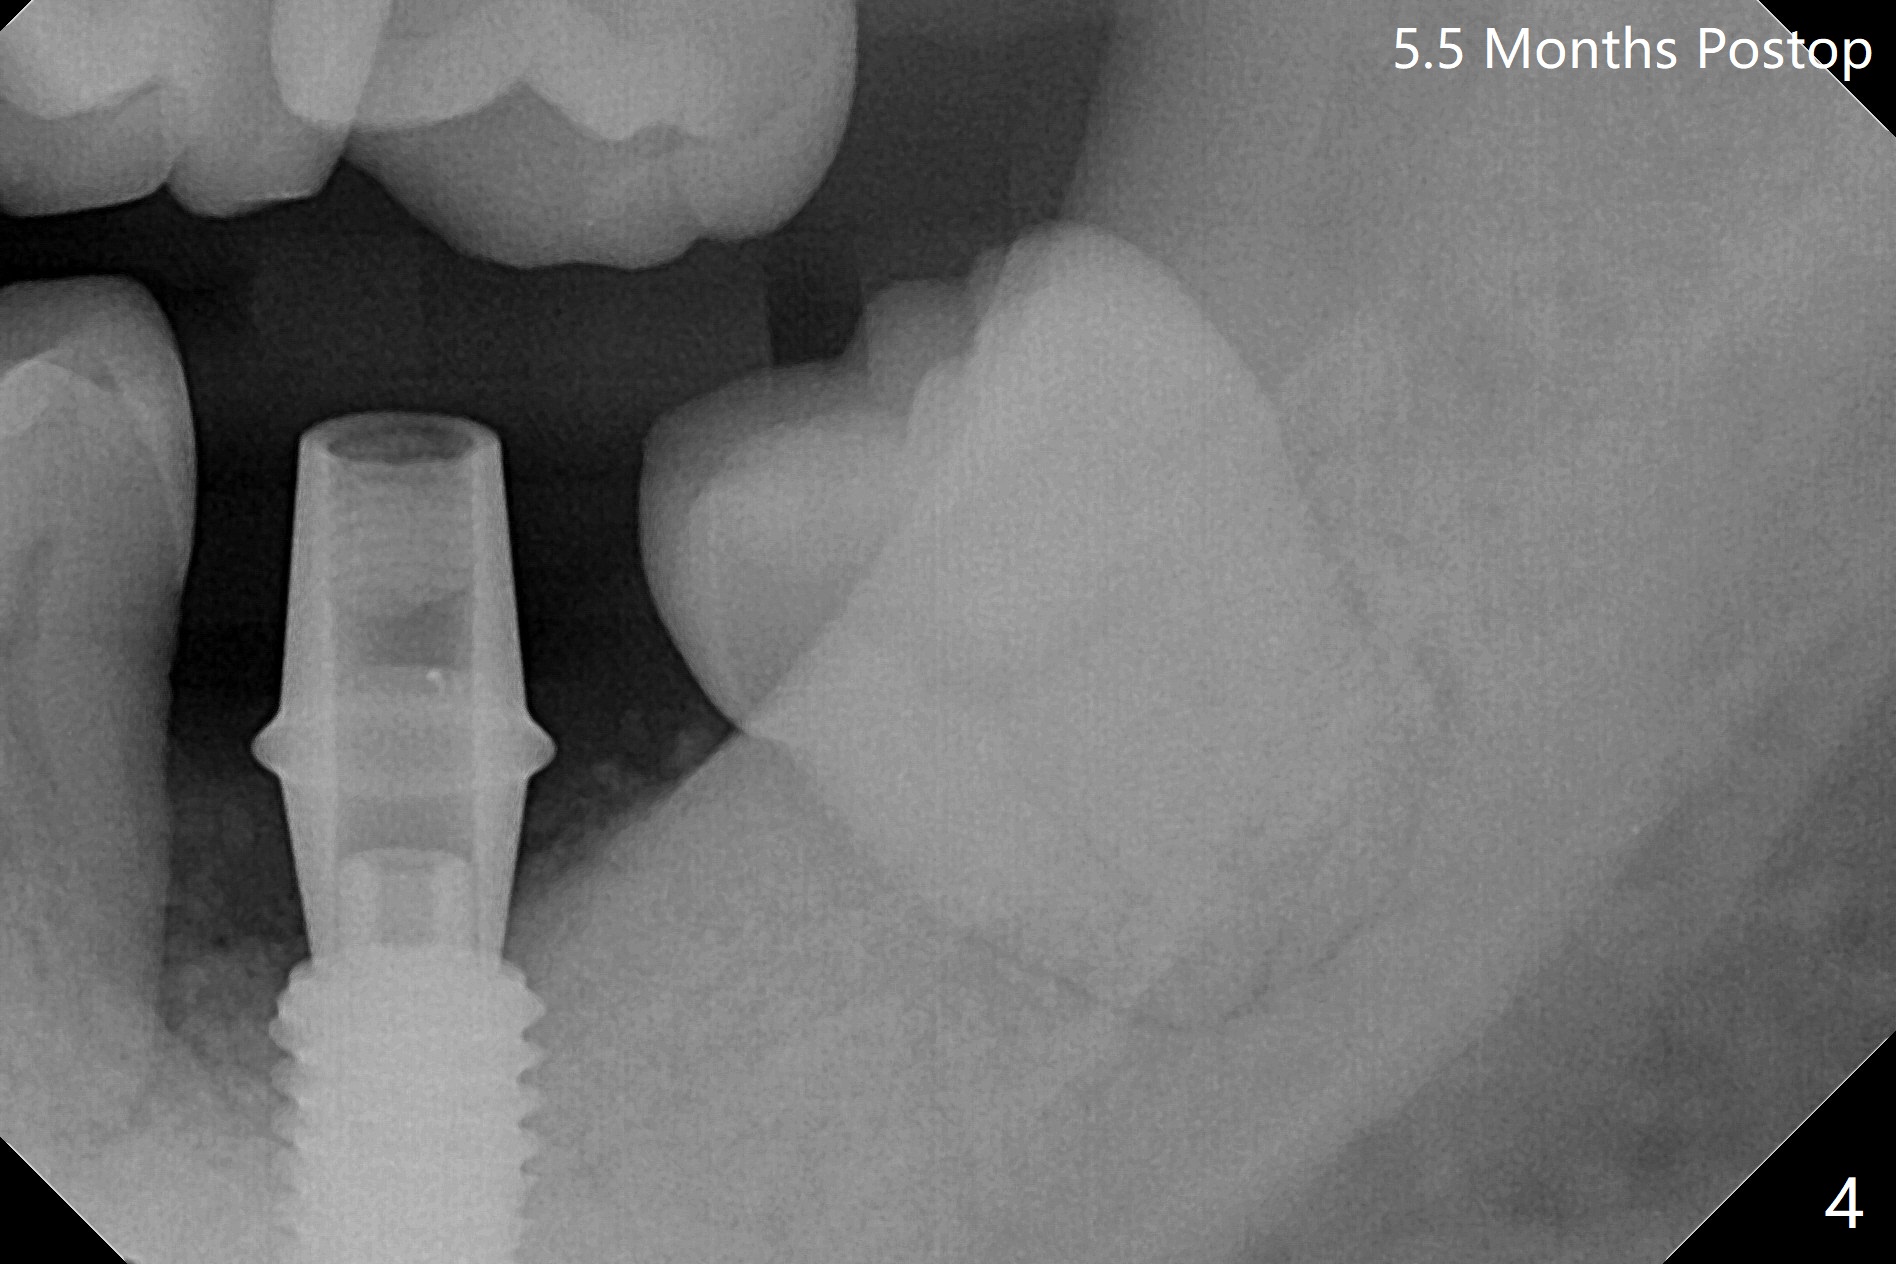

植骨成功必须有两个成分,软硬组织,牙龈提供血运和口袋,而硬组织防止骨粉塌陷。例如即刻植体和基台是可靠,免费(与钛网而言)硬性支撑,今天添加另外一个天然硬性支撑,那就是预后不是很好邻牙。40岁男左下7严重骨质吸收,颊侧,舌侧骨板缺失,骨粉(红色圆圈)将放置6远中,让它发挥余热。8暂时保留,这样7导板稳定些,植入更准确(图一),之后拔除8。结果术中改变计划,得寸进尺,也想保留8,理由骨粉更稳定(图二:*),尤其是远中。6,8牙根面做了刮治。为了证实基台完全就位,又拍摄一张咬翼片(图三),这时植体螺纹清晰。植体与基台之间有两个重要接触部分,第一,图三空箭头,两者必须完全融合(必须没有间隙),理论上可以形成冷焊接(cold welding);第二,短箭头,公母六角形(hex)相接,之间有间隙。如果初步稳定性低,选择愈合基台,与植体交接也必须有X光片验证,两者之间不应该有间隙。如果有间隙,愈合过程,愈合基台很可能脱落,造成病人不安,增加我们工作量,破坏临床进展。图三:术后即刻。术后5.5月(图四)骨粉丧失许多,牙冠外面使用牙周敷料或者直接使用树脂敷料,可能会减少骨粉流失。临床上智齿近中好像没有明显倒凹,取模,估计以后食物坎塞不会太严重。术后6月(牙冠粘固,拧紧25Ncm,图五),螺纹没有暴露。